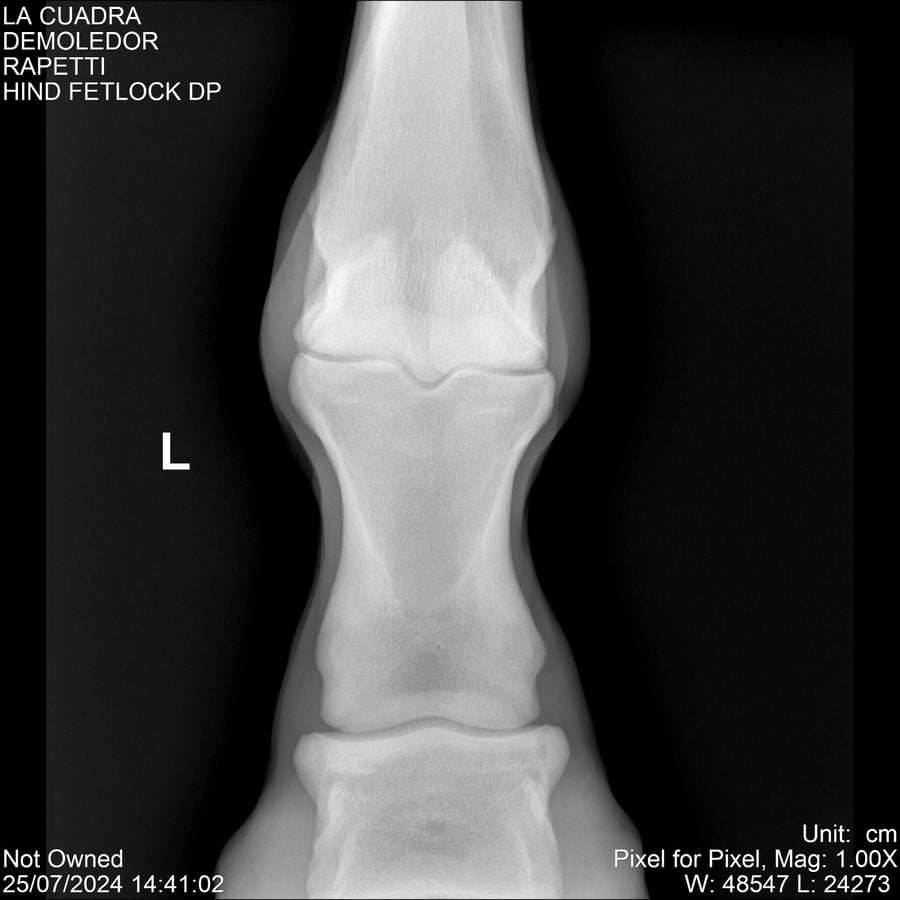

LOTE 14, DEMOLEDOR 🔥 🔥 🔥 Lote Anterior Volver al remate Lote Siguiente Ficha Contacto Montevideo - Ficha del Lote Identificador: #284454 Categoría: Yeguarizos Montevideo - 89 Visualizaciones ClicData Contacto Empresa: Abelenda N. R., Walter Hugo Nombre*: Teléfono* : E-mail* : Mensaje Enviar Registrese gratis Este contenido Exclusivo está disponible sólo para usuarios registrados Ingresar